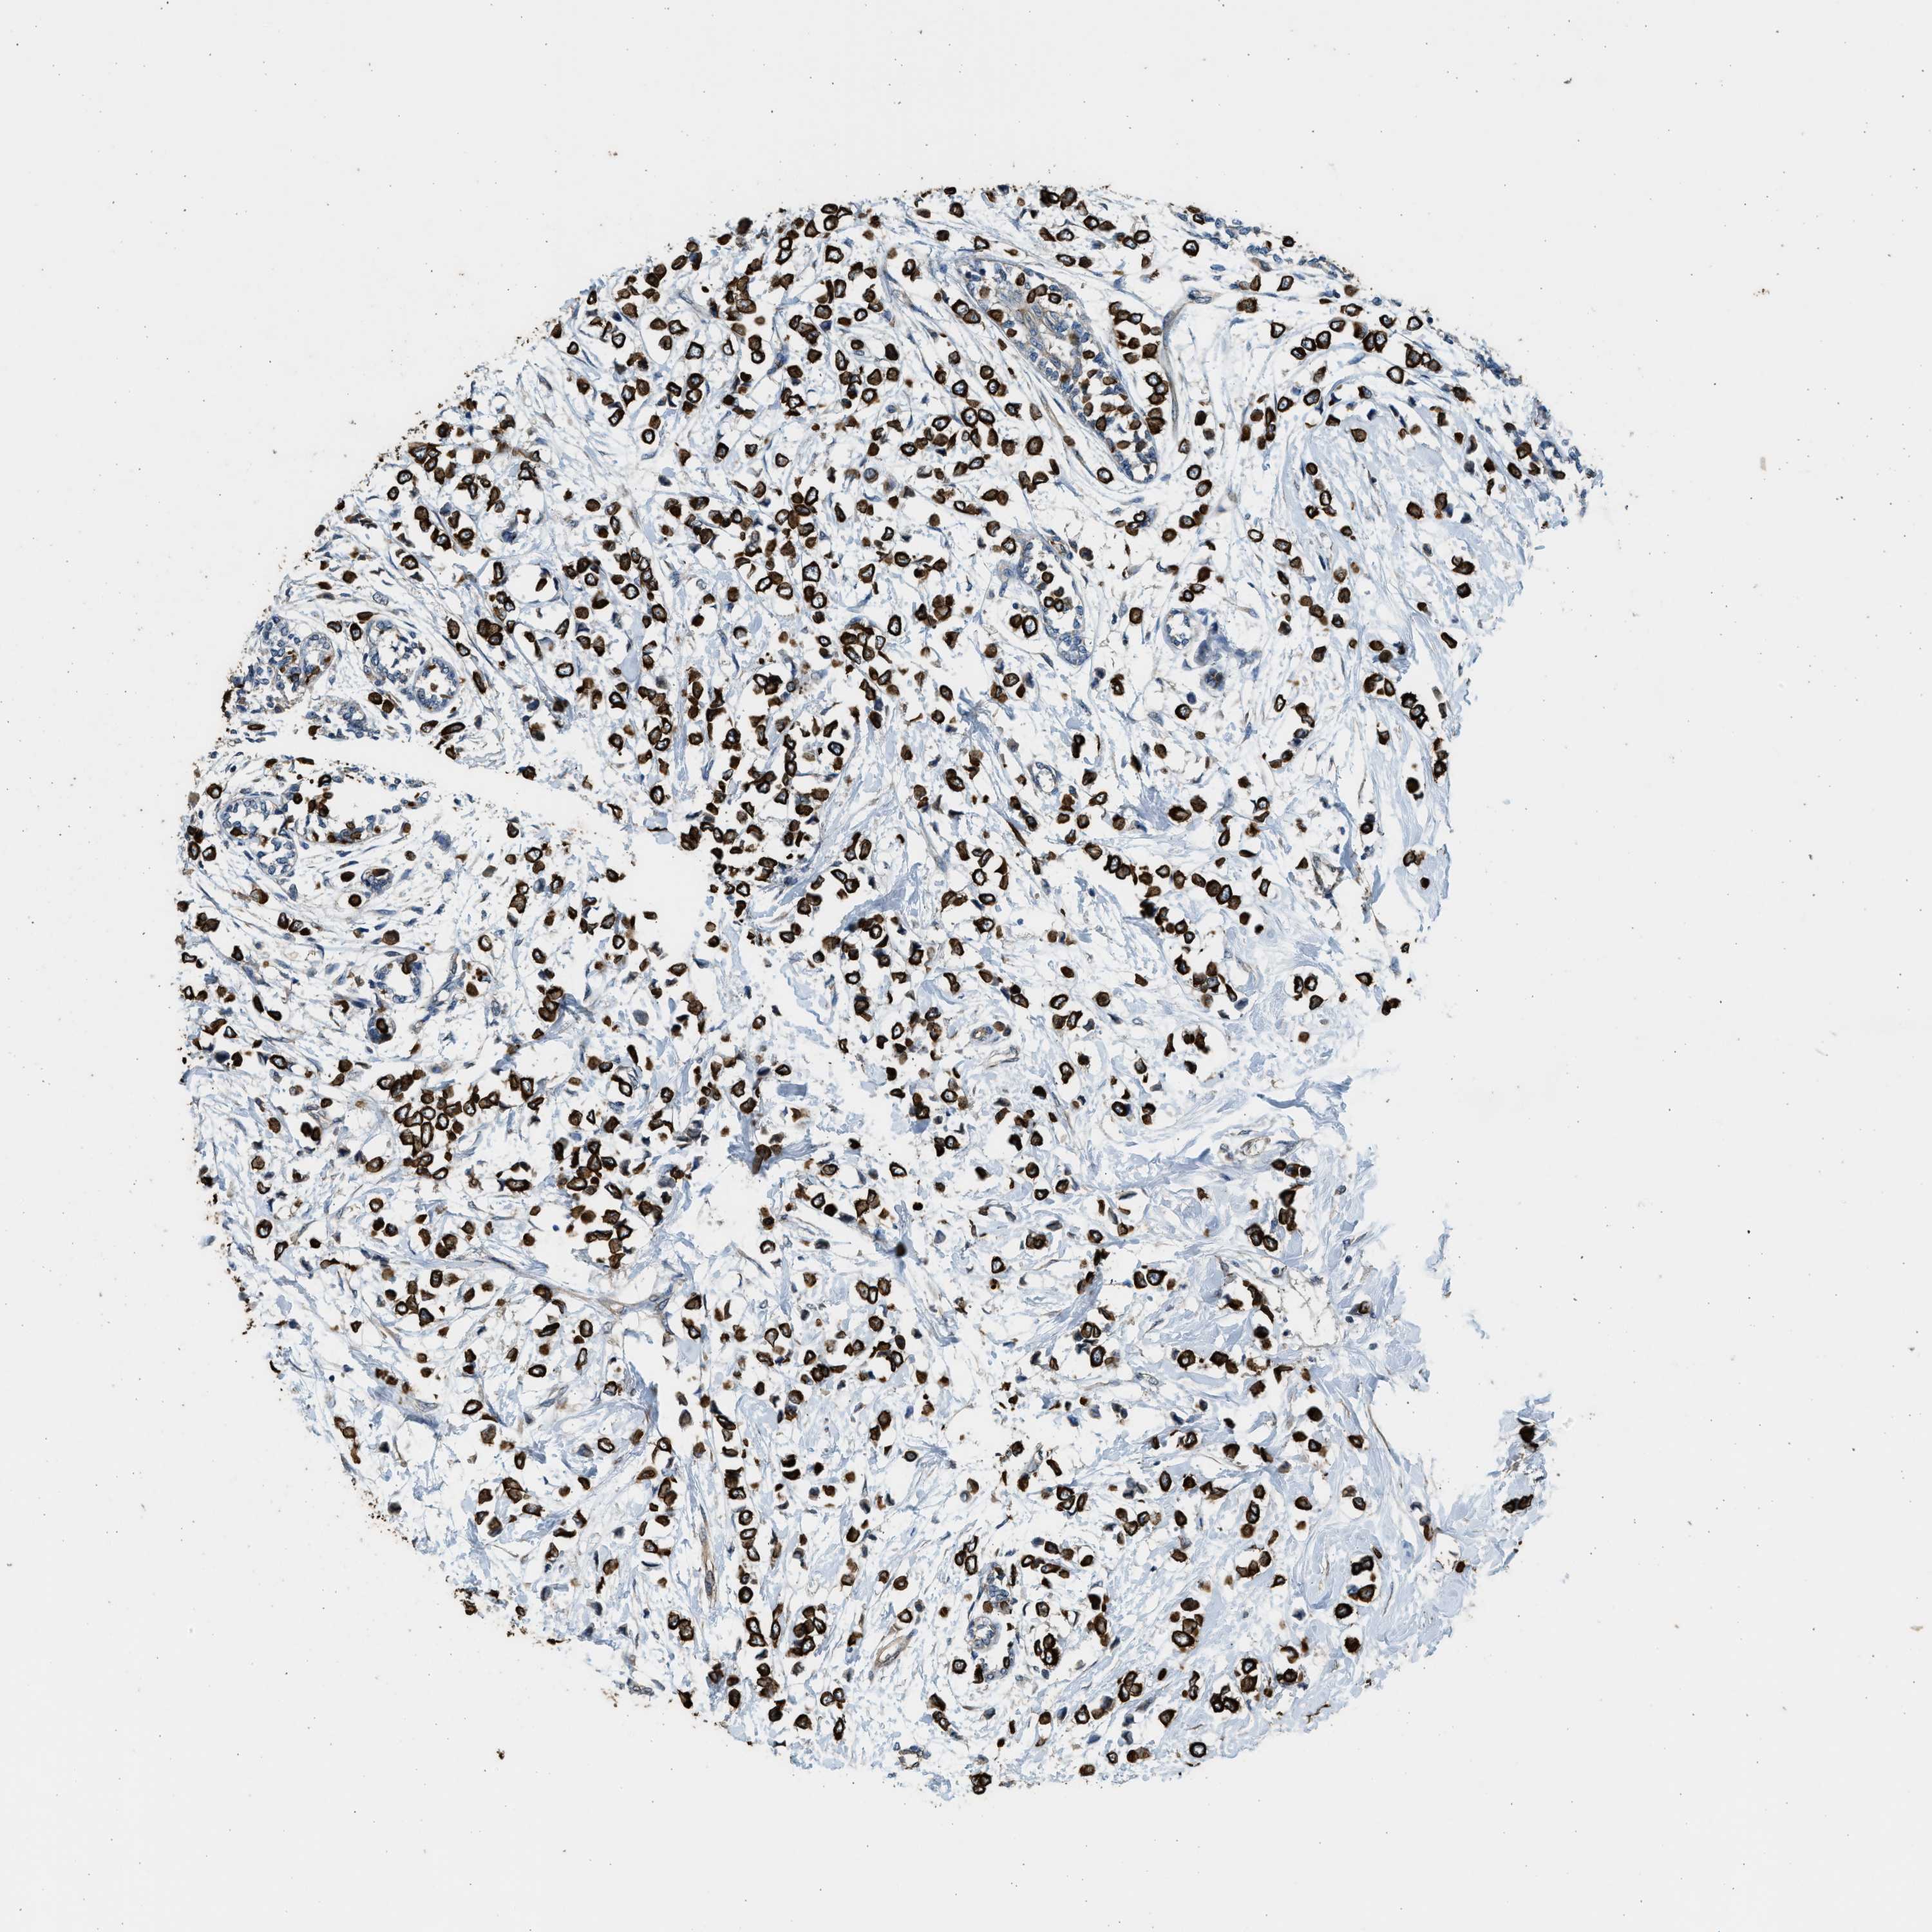

CANCER BREAST CANCER Show tissue menu

BRCA TCGA BRCA VALIDATION PROTEIN EXPRESSION